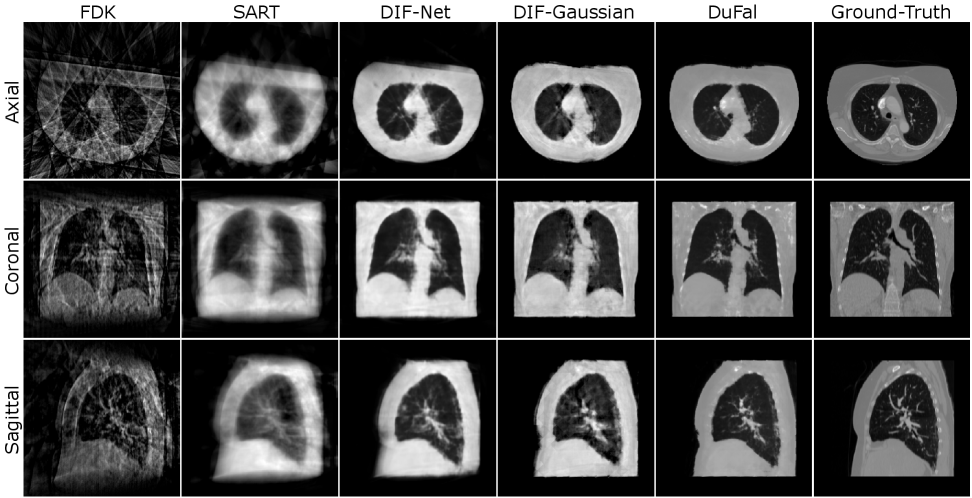

Refer to caption

Figure 4: Visualization of 10-view reconstructed chest CT (from top to bottom: axial, coronal, and sagittal slice). This figure highlights the key advantage of our method in preserving fine details. While DIF-Net and DIF-Gaussian successfully recover the general anatomy, they produce overly smoothed images that lose high-frequency information, as evidenced by the blurry details in the zoomed-in views. In contrast, our method yields visibly sharper reconstructions across the axial, coronal, and sagittal planes, achieving a fidelity much closer to the ground-truth image.

5.3 Qualitative Analysis

We present visual comparisons to further demonstrate the differences between our model and baseline methods. We focus on 6-view reconstructions as this represents the most challenging sparse-view scenario and best showcases reconstruction quality differences (Figures 4 and 5). Traditional methods such as FDK(Feldkamp et al., 1984) and SART (Andersen and Kak, 1984) exhibit noticeable artifacts and fail to preserve fine anatomical structures, while DIF-Net (Lin et al., 2023) and DIF-Gaussian (Lin et al., 2024a) show improvements but still struggle to capture critical high-frequency details and tissue boundaries. Our model produces reconstructions with enhanced clarity and accurate contrast representation, effectively preserving high-frequency features while minimizing artifacts. On the ToothFairy dataset, similar patterns emerge: traditional methods fail to recover fine dental structures. Our approach demonstrates improved capability in reconstructing sharp boundaries and complex anatomical features while maintaining high fidelity under sparse projection conditions across different medical imaging domains.